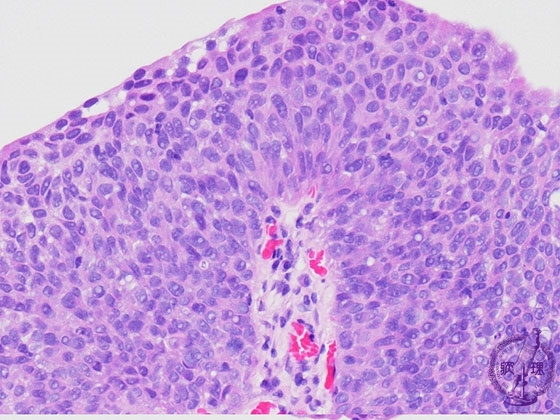

尿路上皮癌(移行上皮癌、G3)ミクロ像(HE強拡大)

ミクロ像(HE強拡大):G3。癌細胞の核密度は非常に高く、N/C比の増加やクロマチンの増量が認められる。